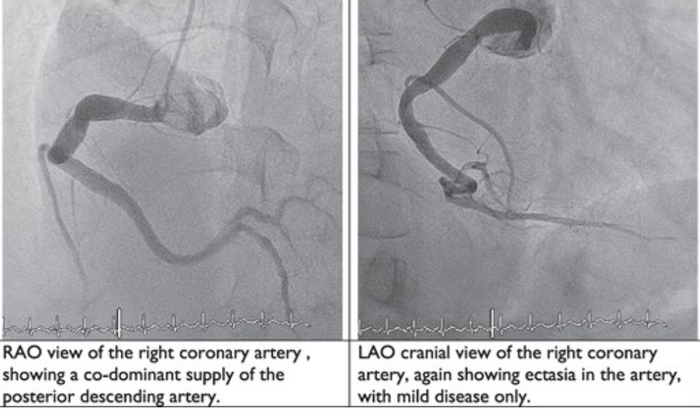

A mysterious cause of myocardial infarction: look beyond his coronary vessels

What do these images tell you? What is the most likely diagnosis?

1. Infective endocarditis

2. Polyarteritis nodosa

3. Systemic lupus erythematous with fibromuscular dysplasia

4. Takayasu arteritis